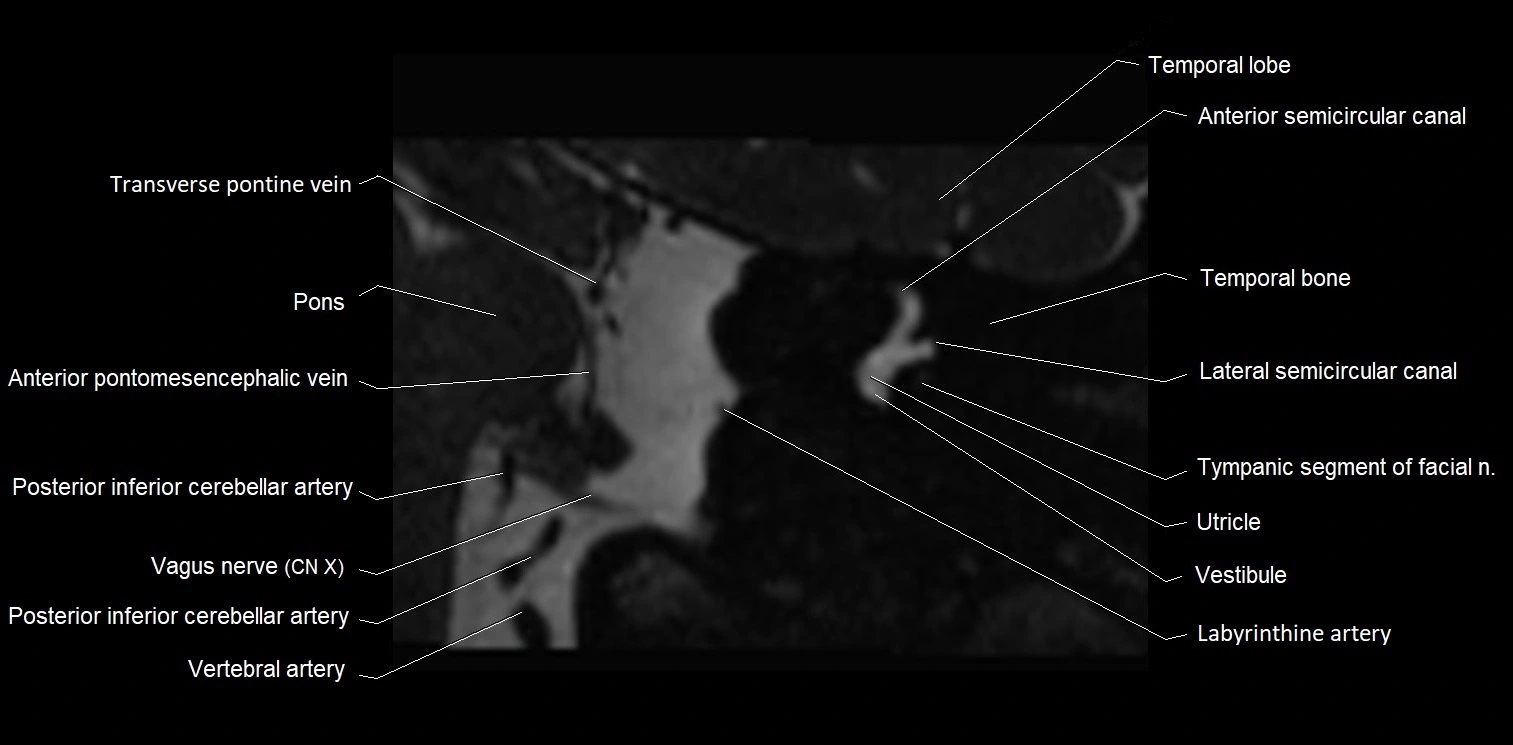

MRI Appearance

• The abducens nerve is a small, thin, linear structure

• Best visualized on high-resolution T2-weighted 3D MRI sequences (e.g., FIESTA or CISS)

• Seen as a hypointense (dark) line running from the brainstem at the pontomedullary junction, traversing the prepontine cistern, and entering Dorello’s canal under the petrosphenoidal ligament, then into the cavernous sinus, and finally the orbit

• May be challenging to visualize in standard MRI due to its small size

• Pathology may be inferred by absence, displacement, or enhancement of the nerve